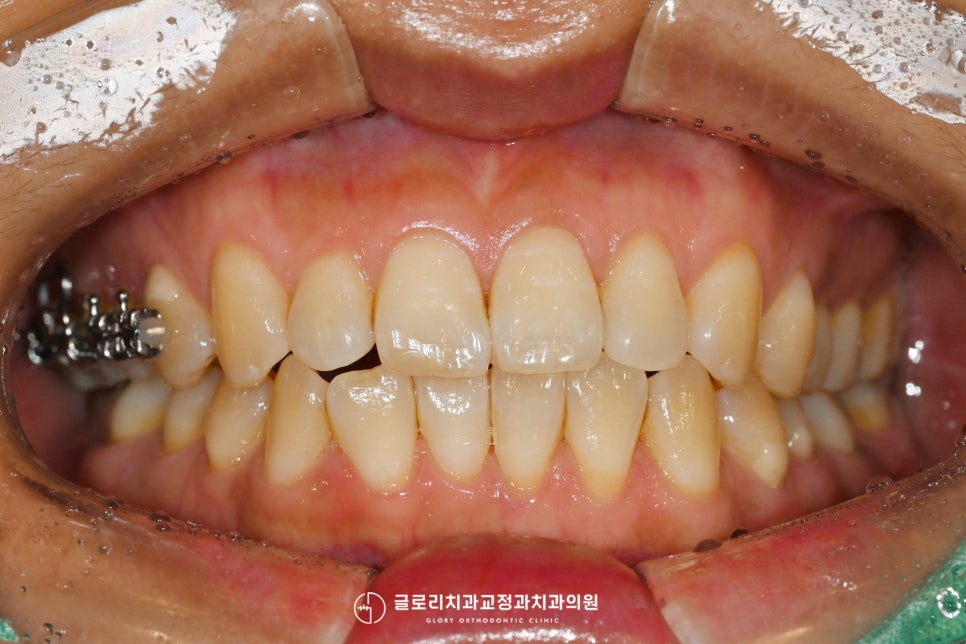

뺨 쪽으로 닿는 치면에는 브라켓을 붙이고

구개면과 가까운 곳에는

버튼을 부착했습니다.

이 과정을 통해 잇몸에 미니 스크류라는

작은 나사를 박아 견인을 도왔는데요.

이렇게 미니 스크류와 구개면에 부착한 버튼에

파워 체인을 연결하여 함입을 도왔는데요.